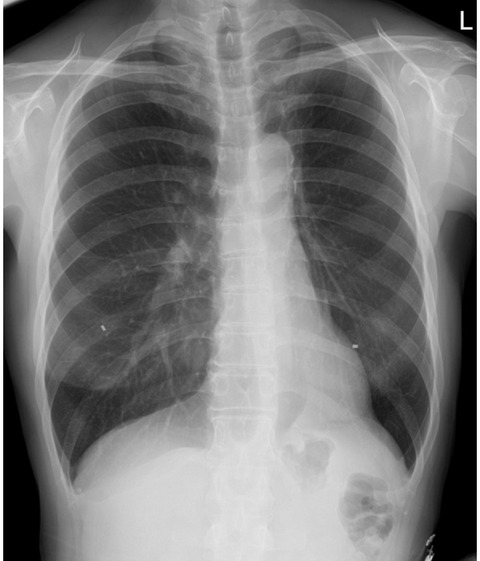

先生はレントゲン画像を見ながら、いつも通り大きな声で笑いながらおっしゃった。

「全然問題ないね。肺も、こんなに伸びてる。手術からどれくらいだっけ?」

「じゃあ、次はまた4ヶ月でX線。最近の調子はどう?」

会計でいつも通り支払いを済ませても、診察予定時間より早く終わった。支払額は、いつも通りの、医師診察料600バーツ(たった3分!)、診察パッケージ代350バーツ、X線650バーツ 合計1600バーツ(5,520円)。まあ、画像データはLineの受診記録からダウンロードもできるし、毎回先生の診断書も出してもらえるので、3分で何もかも終わるわけではないけれど。

現在の体調は4か月前の検診時と変化はない。でもこれを書きながら、もう2年が過ぎたのだと思った。私のがんはⅠAという初期で発見してもらえたので、転移や再発の可能性はほとんどないと言ってもらえた。でもほとんどないと言っても100%ないわけではない。ただ2年過ぎて、かなり気持ちが楽になっているのは事実だ。